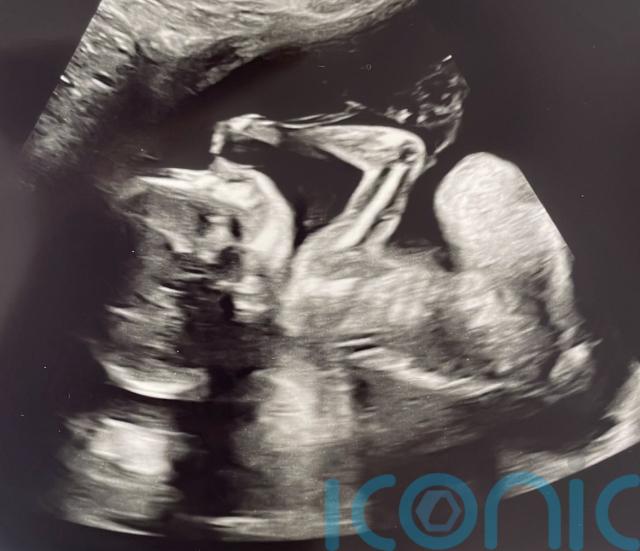

But, at 15 weeks, a private gender scan revealed their baby boy was “missing his left hand” and further tests confirmed he had amniotic band syndrome.

Tom and Faith, who live in Middleton St George, County Durham, said doctors explained that a band had “severed” their baby’s left hand from the mid-forearm down.

At 15 weeks, they had a private scan to determine the gender and were told they were having a boy but they could not detect his left arm.

They were then referred to Darlington Memorial Hospital, where it was confirmed “that the baby’s hand was missing”, and doctors suggested further tests in case “he was severely poorly”.

They were subsequently referred to the Royal Victoria Infirmary in Newcastle where it was confirmed their baby had amniotic band syndrome.

Doctors explained that a band had “severed” his left hand from the mid-forearm and that he would not have felt any pain, as his “pain receptors had not developed yet”.